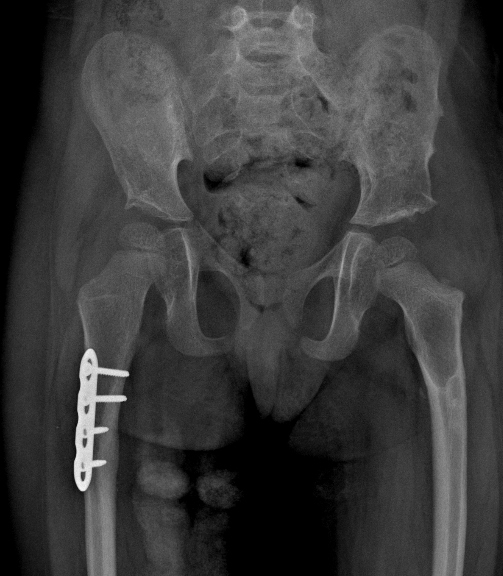

Osteotomia correttiva, innesto osseo omologo, stabilizzazione con placca e viti

Placca e viti: buona congruità articolare, guarigione dell’osteotomia